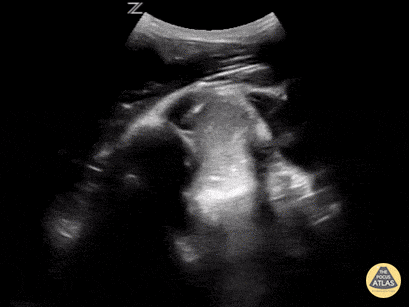

This is a posterior approach looking at the left shoulder showing an anterior dislocation. The dislocation was found before X-ray was shot. While the resident was performing the Cunningham technique to reduce the shoulder, the attending was able to, in real time, watch it go back in place. In between the humeral head and the glenoid rim is a large hematoma where I would aim my needle if I were to do an intra-articular block. It is a helpful technique in those recurrent dislocators. Saves the initial X-ray, but probably should get the post-reduction film at this point. Matt Rutz, MD - Indiana University Department of Emergency Medicine, Ultrasound Division